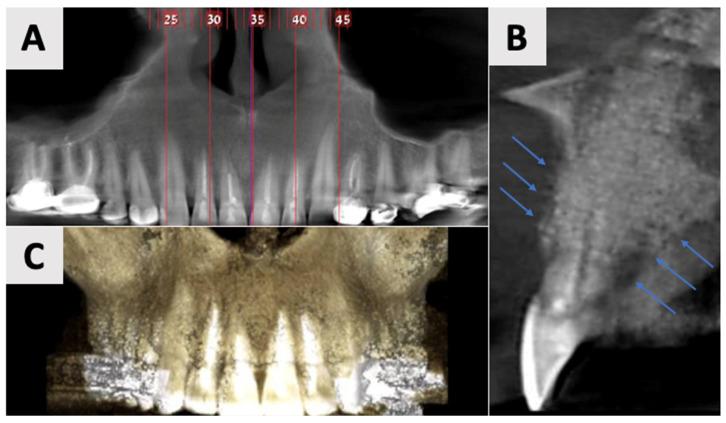

A 35-year-old male patient presented with a large periapical cystic lesion in the maxillary anterior region. Treatment involved marsupialization followed by cyst enucleation and GBR using a resorbable magnesium membrane and bovine xenograft. The magnesium membrane served as a structural support to bridge the bony discontinuity in the palatal bone. Cone-beam computed tomography (CBCT) was used for diagnosis, treatment planning, and follow-up assessments. At 16 months post-treatment, CBCT imaging revealed significant bone regeneration, with restoration of the palatal contour and cortication of the palatal wall. Clinical examination showed asymptomatic teeth with normal mobility and optimal soft tissue healing.

一名35岁男性患者上颌前部出现一个大的根尖囊性病变。治疗包括袋形术,随后进行囊肿摘除术,并使用可吸收镁膜和牛异种移植物进行引导骨再生。镁膜作为一种结构支撑物,用于桥接腭骨的骨不连续处。锥形束计算机断层扫描(CBCT)用于诊断、治疗计划制定和随访评估。治疗后16个月,CBCT成像显示骨再生显著,腭轮廓恢复,腭壁皮质化。临床检查显示牙齿无症状,松动度正常,软组织愈合良好。